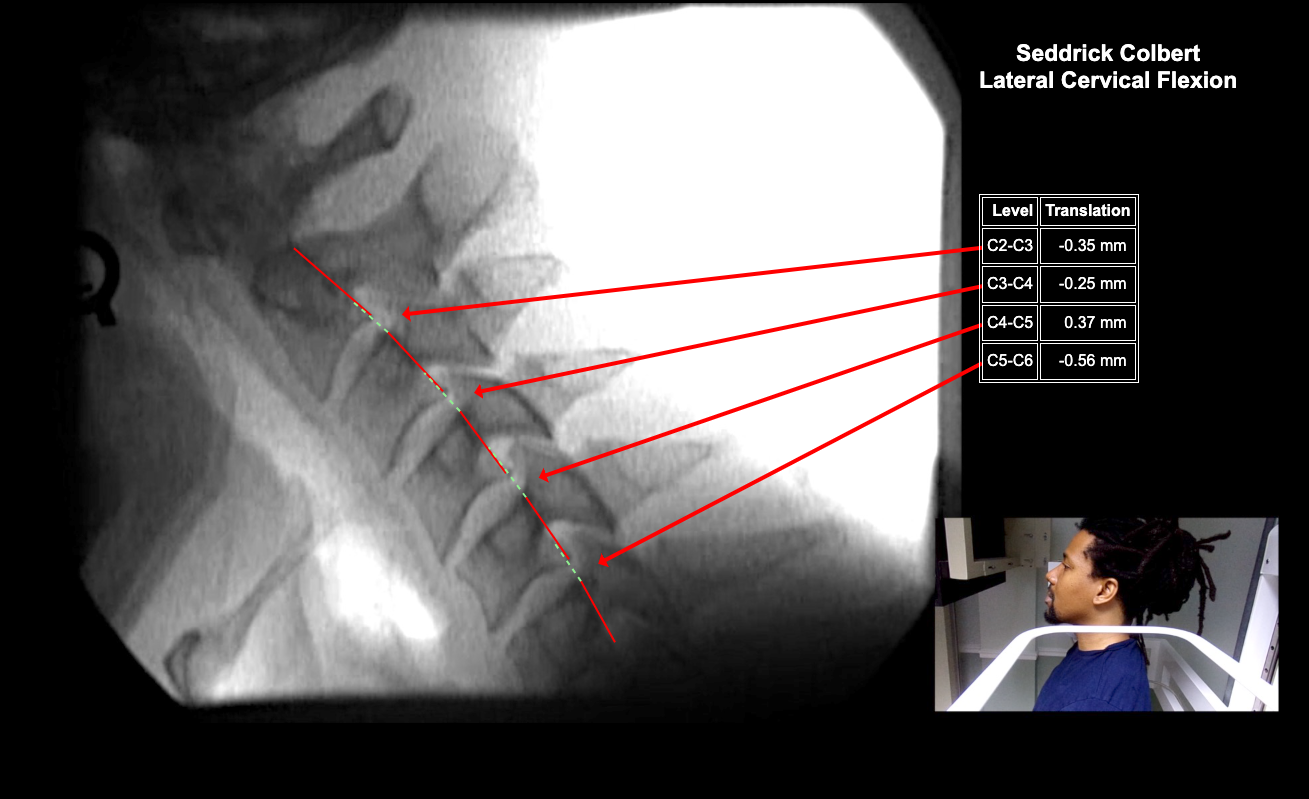

Home > 35 Seddrick Colbert 5-22-25